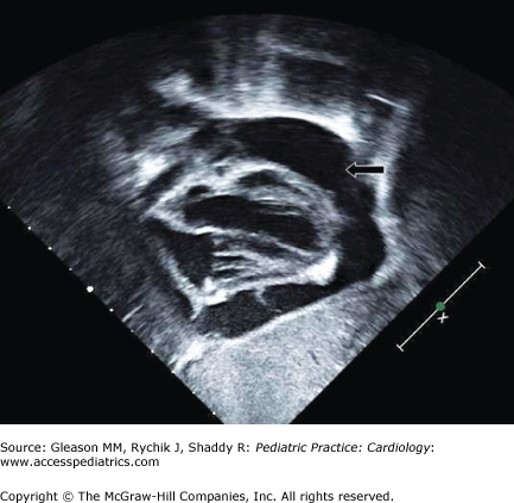

Large pericardial effusion (black arrow) in patient with Kawasaki disease.

Source: Gleason M, Rychik J, Shaddy R. Pediatric Practice: Cardiology; 2012.